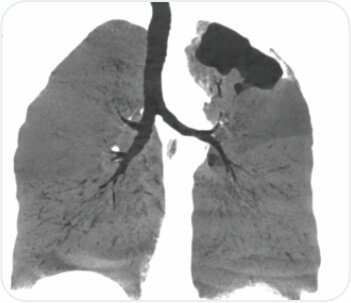

সিটি বুক বাম উপরের লোবে গহ্বরের ইঙ্গিত দেয়। এফওবি বাম উপরের লোব ব্রঙ্কাস থেকে পুস নির্গত হওয়ার পরামর্শ দিয়েছিল এবং বাম উপরের লোব ব্রঙ্কাসে একটি জমাট ভরের সাথে অনুগত। পরবর্তী ব্রঙ্কোঅ্যালভিওলার ল্যাভেজ প্রধানত নিউট্রোফিলিক ছিল। পাইজেনিক, ছত্রাক, যক্ষ্মা এবং নোকার্ডিয়ার জন্য দাগ এবং সংস্কৃতি নেতিবাচক ছিল। সাইটোলজি ম্যালিগন্যান্সির জন্য নেতিবাচক ছিল। ইনভেসিভ মিউকোরমাইকোসিসের একটি নির্ণয় করা হয়েছিল।

অনমনীয় ব্রঙ্কোস্কোপি + প্রোট্রুডিং ভরের ক্রায়োবায়োপসি + এন্ডোব্রঙ্কিয়াল ব্লকার (ফগার্টি বেলুন) করা হয়েছিল।

সিটি বুক - বাম উপরের লোবে গহ্বর